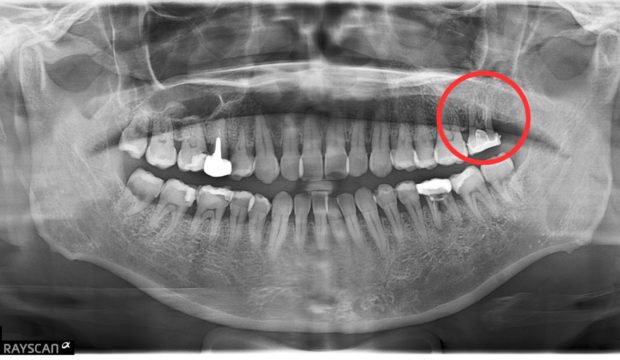

治療

破折等は認められなかった。

抜歯と病変部の除去

歯根切除

術直後のレントゲンと処置後の状態

経過観察 6ヶ月後

術後比較